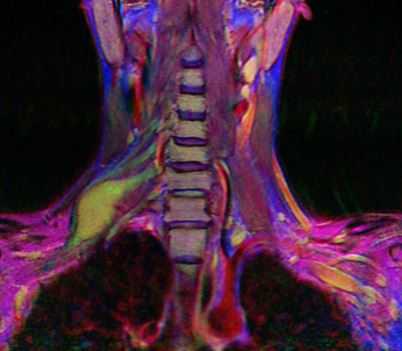

МРТ мягких тканей шеи. Корональная Т2-взвешенная МРТ. Невринома плечевого сплетения справа. Цветовая обработка изображения.

Плечевой сплетение состоит из тесно переплетающихся нервных стволов, отходящих от вентральных корешков нервов шейного отдела (С5-С7) и грудного отдела (Т1) спинного мозга. 3 первичных ствола неоднократно делятся и взаимно соединяются. Плечевое сплетение, в конечном итоге, переходит в нервы верхних конечностей, обеспечивая чувствительную и двигательную иннервацию. Расположено плечевой сплетение в области ключицы.